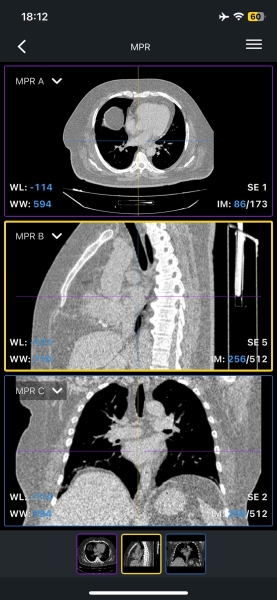

IDV — Imaos Dicom Viewer

Одно из лучших приложений для просмотра DCM, возможностей которого даже в бесплатной версии более чем достаточно для личных целей. Поддерживает все типы исследований, умеет открывать как отдельные файлы, так и целые серии срезов. При этом вся информация обрабатывается и хранится на вашем устройстве без отправки в интернет.

Свайпом по изображениям можно управлять контрастом и переключаться между срезами. В меню доступен переход в различные режимы представления, а также есть выбор активного инструмента на экране: измерения, презентация и другие.